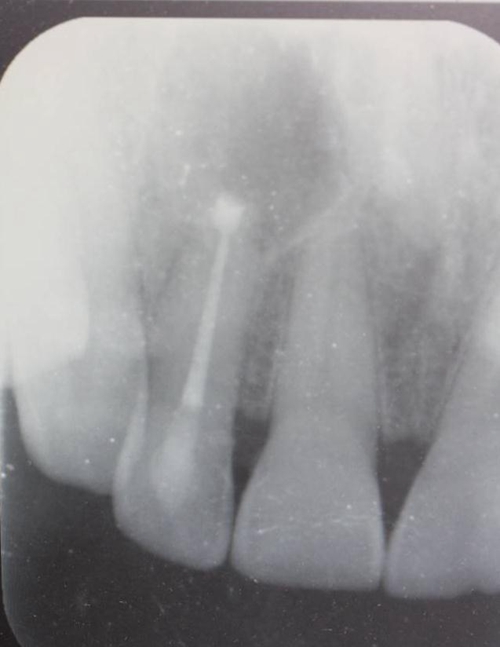

圖1.患者在根管術(shù)前的根尖片影像檢查:12有開髓孔,根尖有橢圓形陰影。

圖2. 12牙齒在我院進(jìn)行熱牙膠根管充填+樹脂充填。